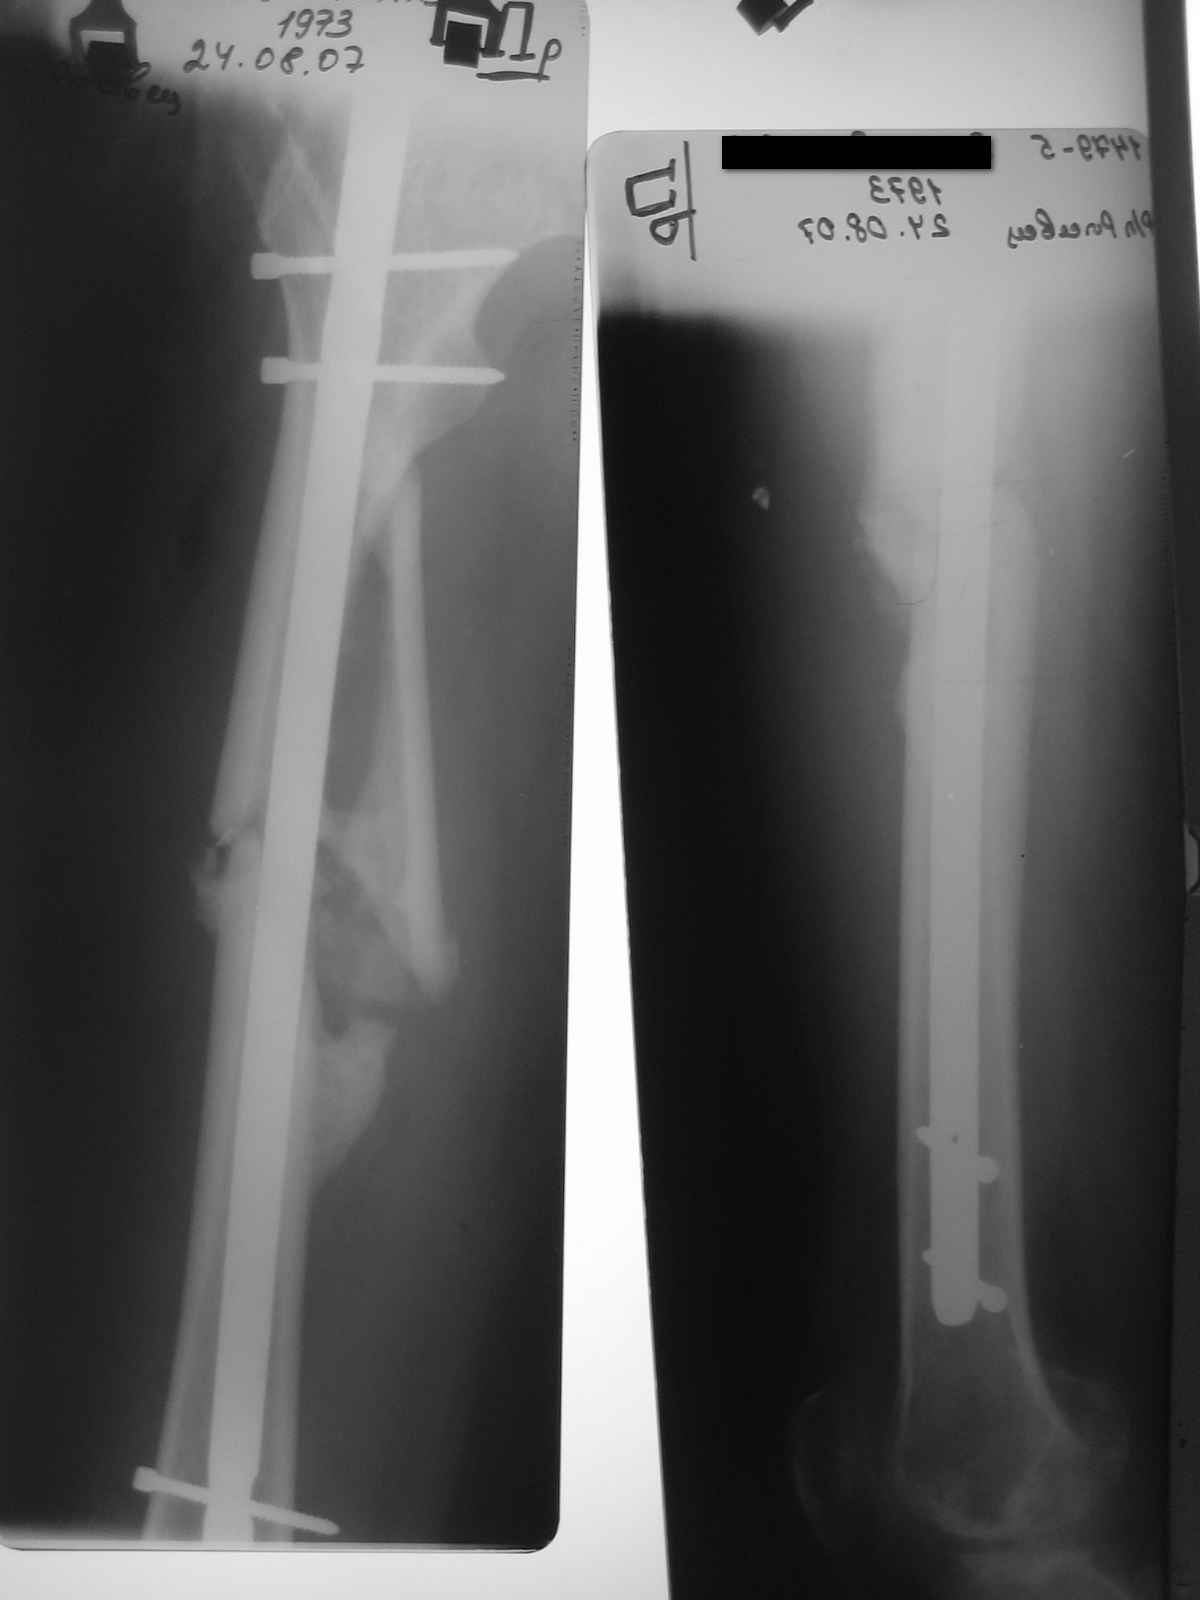

уважаемые коллеги, поступил пациент, через 6 месяцев после травмы, который лечился 3 месяца

на скелетном вытяжении, затем гипс еще 1,5 месяца, дозированная нагрузка через 3,5 месяца

после травмы. Дней 5 назад поскользнулся в ванной, почувствовал боль в бедре, появилась

деформация. Оперирован у нас, произведен остеосинтез блокирующим стержнем ,перелом не

открывался, был "доломан" на столе. меня интересует вариант вальгирования гвоздя в этом

случае. И по-вашему какие ерспективы у этого клиента?